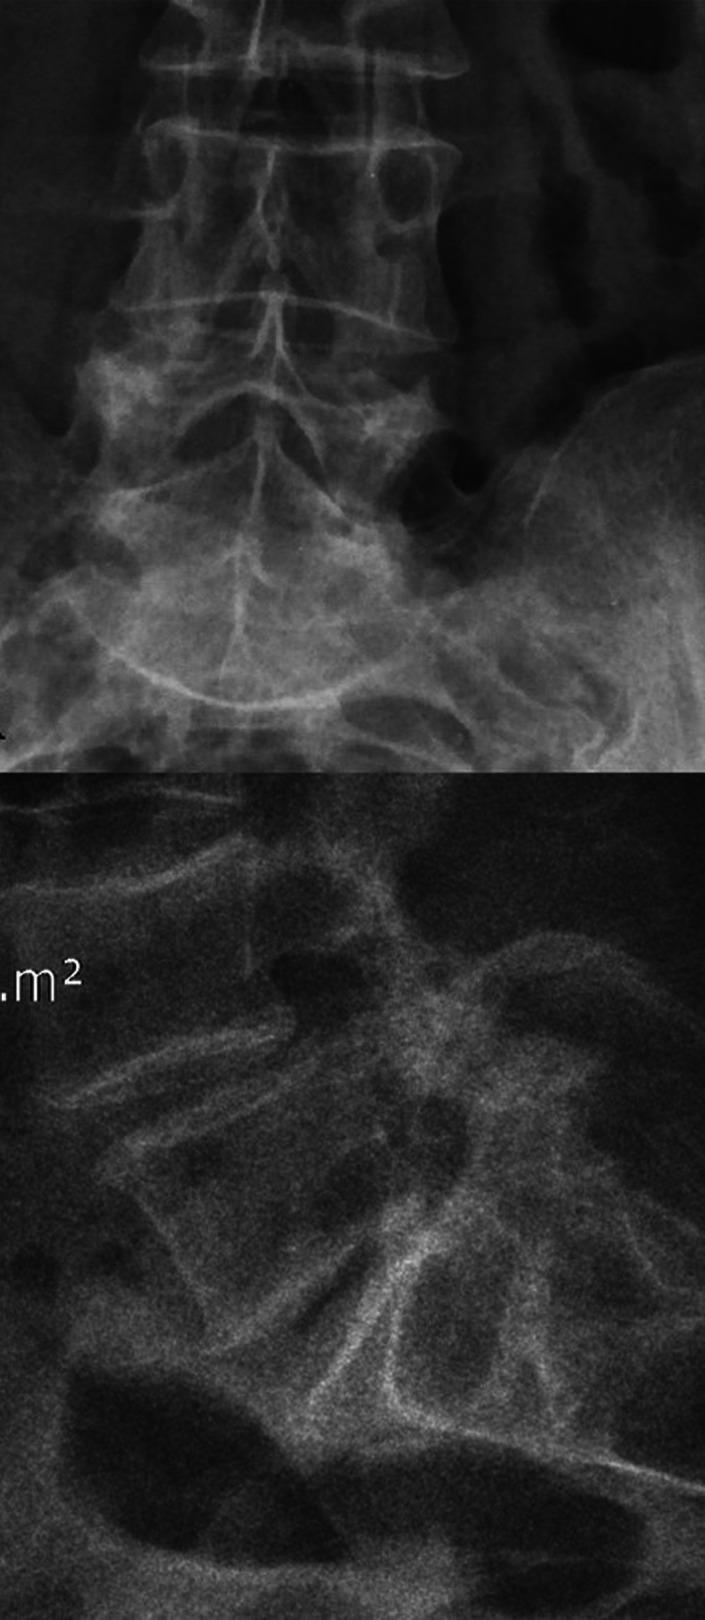

The aim of this study was to evaluate disc metabolism after decreasing the axial load through surgery by assessing the glycosaminoglycan content through a non-invasive method-delayed gadolinium-enhanced magnetic resonance imaging of cartilage (dGEMRIC).

Sixteen patients with mono-segmental disc degeneration (L4-L5 or L5-S1) who underwent posterior lumbar spine fixation with intervertebral distraction of 2 consecutive vertebrae using monoaxial transpedicular screws and lyophilized allograft to achieve segmental fusion, and who had a follow-up period of at least 2 years, were included in this study. The first lumbar disc was used as the control group. The dGEMRIC studies in degenerative and control discs, visual analogue scale (VAS), Oswestry disability index (ODI), lumbar lordosis, and disc thickness were reviewed before and after surgery.

Visual analogue scale and ODI showed significant improvements (P=.003, P=.0004, respectively). The thickness of the operated discs was increased by an average of 2.41 mm (P=.0004) while maintaining lumbar lordosis (P=.35). In pre- and post-surgery dGEMRIC studies, the operated discs showed a significant di!erence (P=.0013), while the control groups remained approximately unchanged (P=.87).

We have demonstrated that by restoring the disc height and reducing the associated pressure, the glycosaminoglycan content can be increased in the discs, as indicated by a decrease in gadolinium binding. Our results suggest that eliminating pressure on intervertebral discs can prevent their degeneration and initiate the regeneration process.

本研究的目的是通过一种非侵入性方法——延迟钆增强磁共振成像(dGEMRIC)评估糖胺聚糖含量,以评价通过手术减轻轴向负荷后的椎间盘代谢情况。

本研究纳入了16例单节段椎间盘退变(L4-L5或L5-S1)患者,这些患者接受了使用单轴椎弓根螺钉和冻干同种异体骨进行连续两个椎体间撑开的后路腰椎固定术以实现节段融合,且随访期至少为2年。将第一腰椎间盘作为对照组。回顾性分析退变椎间盘和对照椎间盘手术前后的dGEMRIC研究、视觉模拟评分(VAS)、Oswestry功能障碍指数(ODI)、腰椎前凸和椎间盘厚度。

视觉模拟评分和ODI均有显著改善(分别为P = 0.003,P = 0.0004)。手术椎间盘的厚度平均增加了2.41 mm(P = 0.0004),同时维持了腰椎前凸(P = 0.35)。在手术前后的dGEMRIC研究中,手术椎间盘有显著差异(P = 0.0013),而对照组基本保持不变(P = 0.87)。

我们已经证明,通过恢复椎间盘高度并减轻相关压力,椎间盘内的糖胺聚糖含量可以增加,这表现为钆结合减少。我们的结果表明,消除椎间盘上的压力可以防止其退变并启动再生过程。